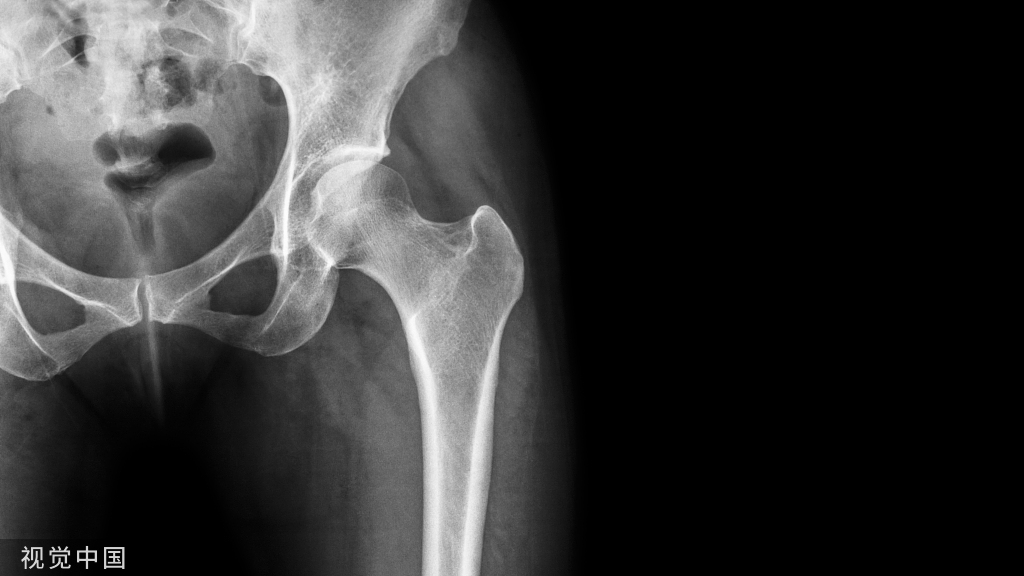

⑩关节内非对称性肿胀(X线照片)。

⑪骨皮质下囊肿不伴有骨质糜烂(X线照片)。